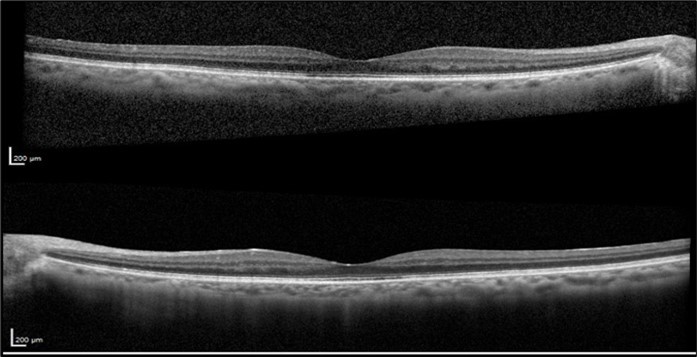

The patient was closely monitored every three months during the first year following the discontinuation of Leflunomide, and then every six months thereafter. Follow-up evaluations included repeated VA tests, fundus examinations, and SD-OCT imaging to assess the resolution of CME and any improvements in visual function. After two years of discontinuing Leflunomide, the CME resolved without recurrence and without the need for any topical treatment. At her final visit, VA was OD 20/25 and OS 20/25. OCT OU revealed resolution of the CME with a dry fovea (Figure 4).

Figure 4.Optical coherence tomography of both eyes revealing the sustained resolution of the cystoid macular edema after Leflunomide discontinuation.